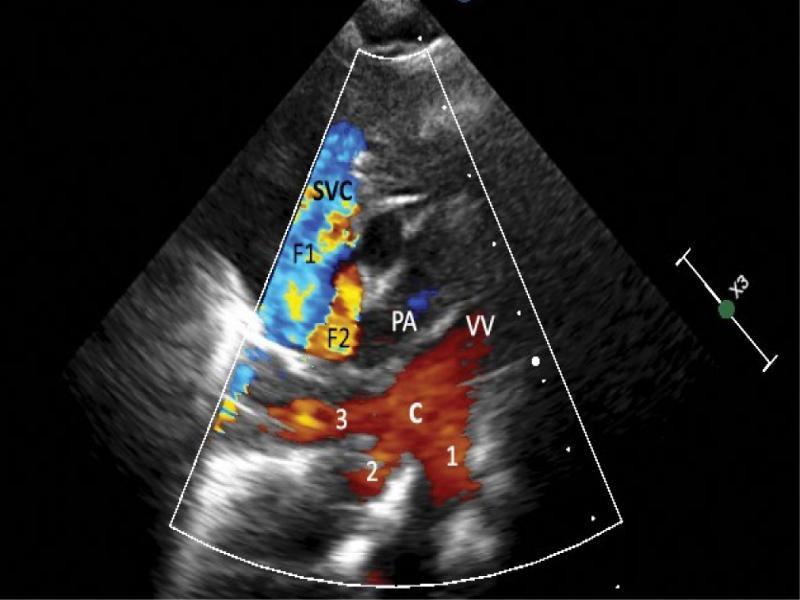

A supracardiac type of total anomalous pulmonary venous drainage (TAPVD) through a 12-millimeter-wide vertical vein with significantly dilated brachiocephalic vein and even more enlarged superior vena cava was diagnosed based on echocardiography (Fig. 1, Fig. 2, Fig. 3, Fig. 4, Fig. 5), and confirmed using CT angiography (Fig. 6, Fig. 7, Fig. 8). A 10 mm secundum atrial septal defect permitted a relatively unrestricted right-to-left atrial flow, and thus the survival of the patient. The right atrium and right ventricle were also enlarged. Echocardiographic signs of pulmonary hypertension were present. The marked dilatation of the SVC and unusual, turbulent flow pattern within this vessel, which was detected on ECHO, suggested that the right upper pulmonary vein drained separately to the SVC. This suspicion was not confirmed by either CT angiography or direct surgical inspection.

Echocardiographic view of upper mediastinum in the frontal plane. Presentation of flow with color Doppler. Diastole. The confluence of the pulmonary veins with two right and one (inferior) left pulmonary veins is visible (1, 2, 3). Also visible are: the connection of the confluence (C) with the left-sided vertical vein (VV), the part of the main pulmonary artery (PA), right pulmonary artery, transverse section of the ascending aorta and superior vena cava, dilated out of proportion regarding the flow it carries. The flow in pulmonary veins and in the confluence is directed upward, therefore is coded red. There is no flow in the arteries (diastolic phase). The flow in the superior vena cava would be expected to be directed exclusively downward and therefore shown in blue (F1); instead, the intensive, continuous red (directing upward) stream of flow (F2) is present close to the left wall of the SVC. This picture strongly suggests a connection of an additional vessel – most likely the right upper pulmonary vein – with the SVC